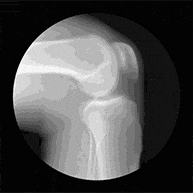

骨性关节炎为一种退行性病变,系劳损等因素引起的关节软骨退化损伤,伴有缓慢发展的关节肿痛、僵硬,甚至畸形。

典型症状 关节对称性疼痛、僵硬、活

动时有摩擦感或“咔哒”声好发人群 20-50岁,多发男性 正确检查 肌骨超声

X线检查等治疗细节 点击在线客服>>